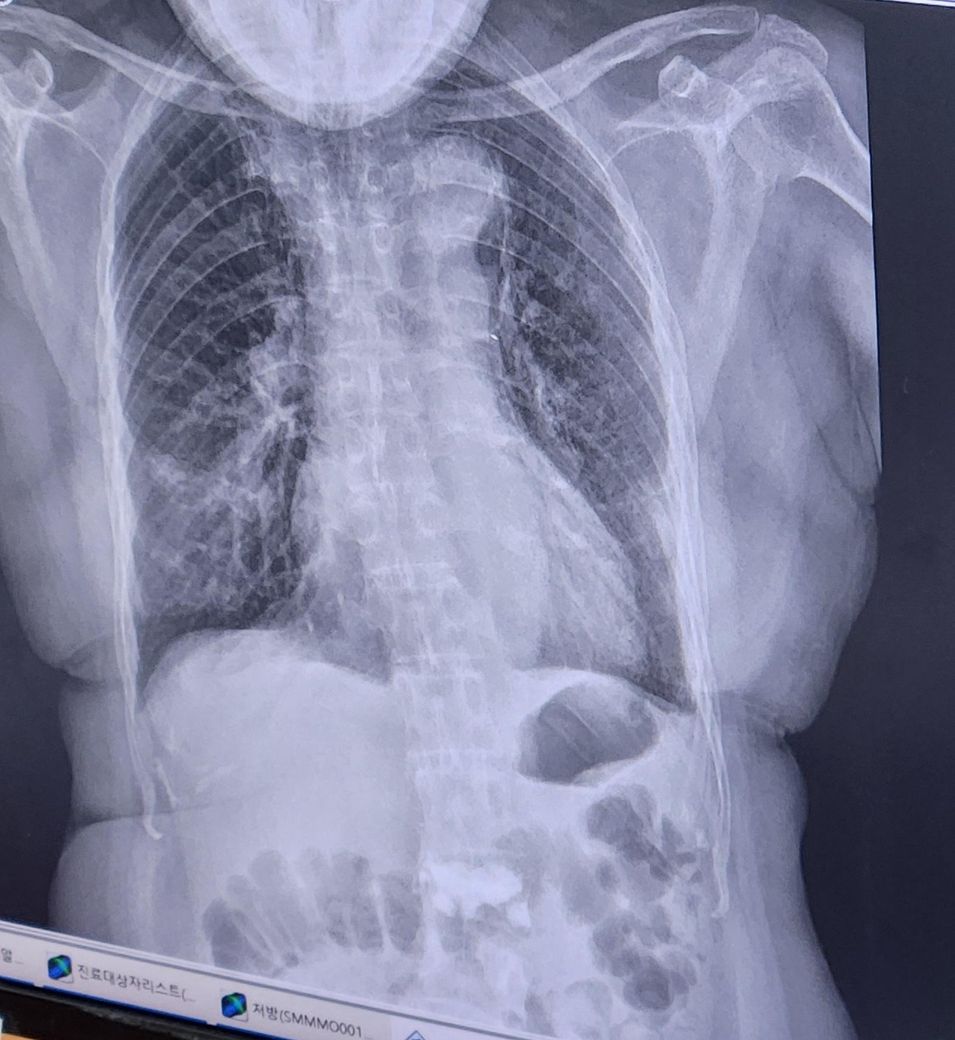

엑스레이를 보니 우하엽에 저명한 폐렴 소견이 의심됩니다.

항생제 치료를 진행하면서 임상적 변화를 보인다니 다행스럽습니다.

문의주신 내용으로 볼때는 폐렴이 호전되고 있는 것이라 조심스럽게 예상 가능합니다.